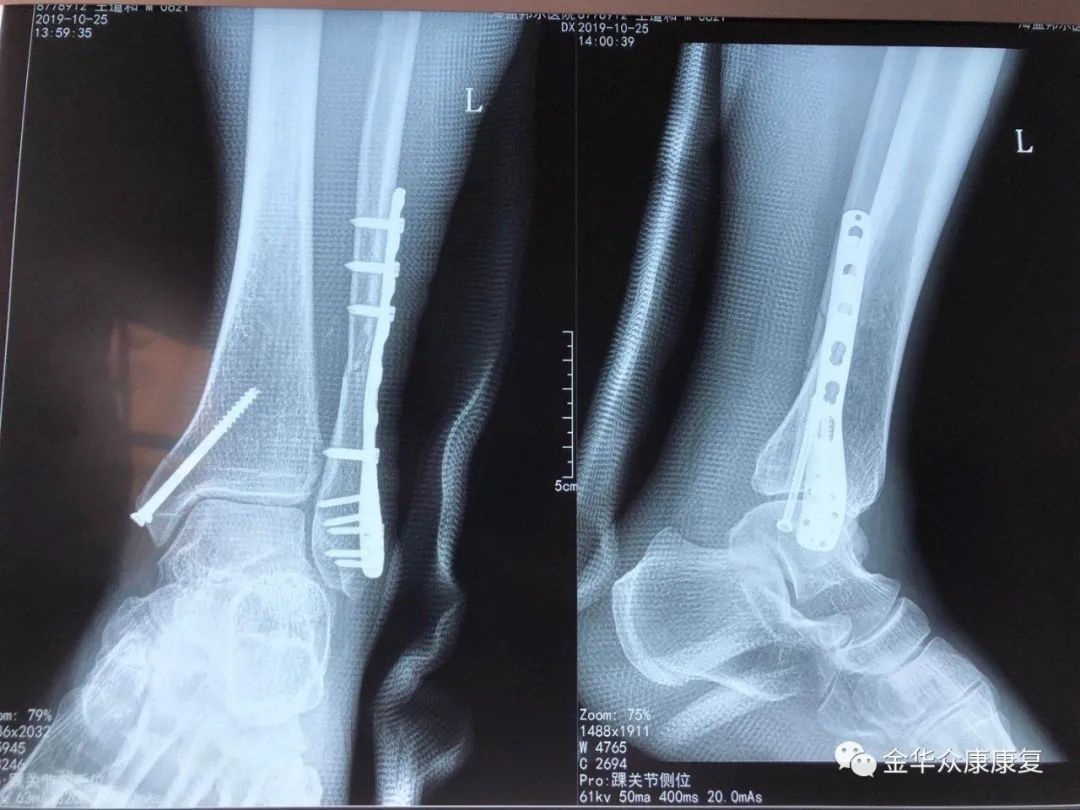

骨科:专业开展急诊创伤、骨关节疾病的治疗,手术及微创治疗四肢、关节骨折、髋膝关节置换、颈腰椎疾病。中医正骨、介入治疗、闭合穿针内固定、经皮撬拔复位、小针刀、水针刀、神经根阻滞、骶管注射、封闭、骨牵引等多种治疗手段。